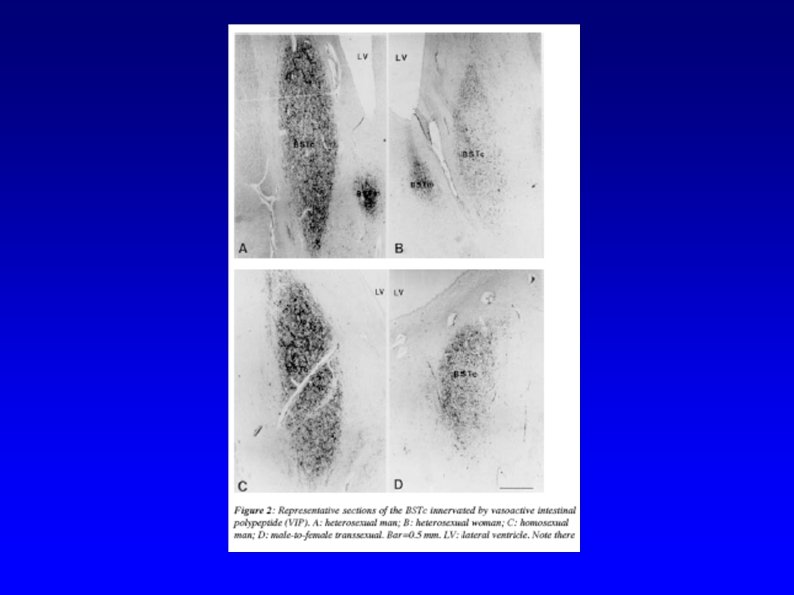

Etiology § Nature vs. nurture? § Anatomic evidence § BSTc § 2 D: 4 D Ratios